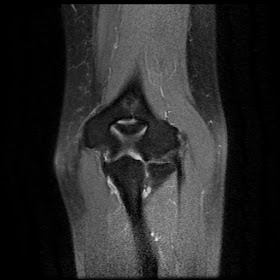

Bucket Handle Tear

"Double PCL" Sign